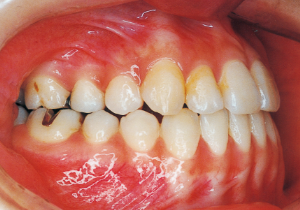

2 After Phase 2 Treatment 5-9-’92

3 Initial Visit 8-29-’79

4 Initial Visit 8-29-’79

Although there were many missing deciduous teeth, the number of permanent teeth was not problematic (4). The amount of negative overjet was significant (1). On cephalometric radiographs, the mandibular ramus was not relatively long, but the large gonial angle and the long mandibular body were noticeable, indicating an overall tendency of the mandible to project inferiorly and anteriorly. High lower facial height was also characteristic.

A potential predisposition to mandibular protrusion was clearly evident.